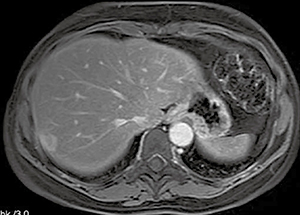

■ダイナミック撮像手法:TIGRE

3Dの高空間分解能を要するダイナミック撮像では,高速撮像技術,脂肪抑制技術,3D撮像技術などの総合技術が要求される。これに対応するため,脂肪抑制パルスを併用した3D高速T1強調RFスポイルドグラディエントエコーシーケンス“TIGRE(T1 weighted GRadient Echo nature of the sequence)”を搭載した。

高い病変検出を実現するためには安定した脂肪抑制が重要である。TIGREは脂肪抑制効果を保ちつつ,ダイナミック評価に十分な時間分解能を得るため,脂肪抑制パルスとしてH-sincを部分的に印加する。これにより,広いFOV撮像においても,均一な脂肪抑制効果が得られる。

図4に,体幹部のTIGRE画像例を示す。広い範囲で良好に脂肪が抑制され,息止め状態で高速な3Dダイナミック撮像を行うことが可能である。

図4 TIGRE画像例